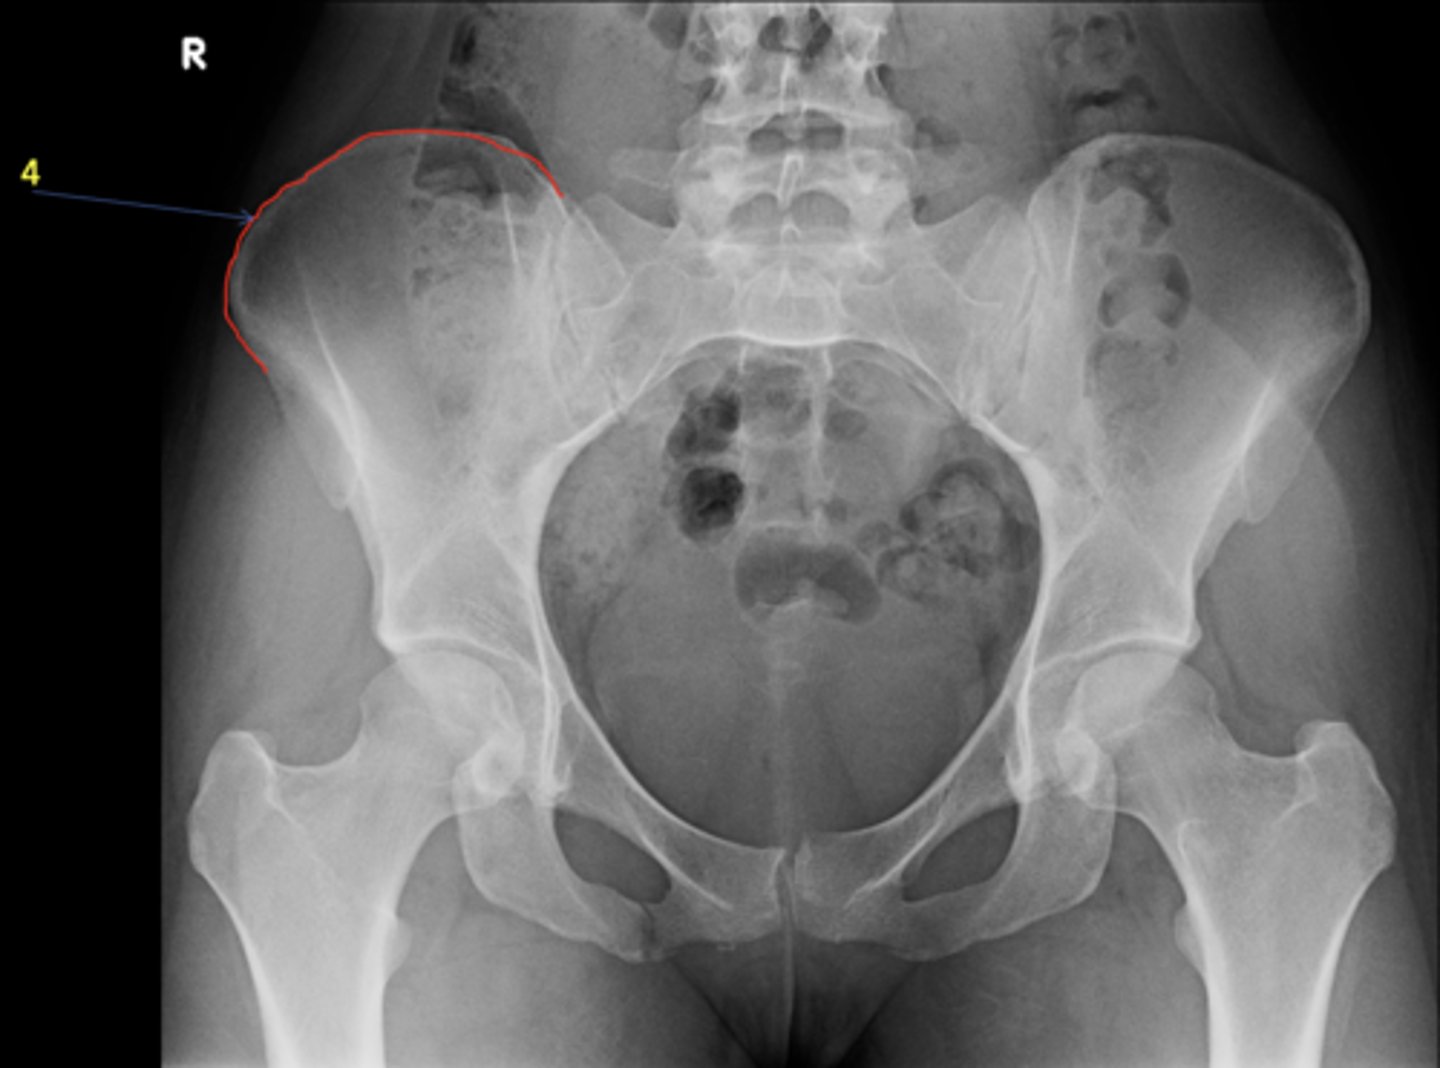

1

New cards

AP pelvis

View?

<p>View?</p>

2

Right lesser trochanter

ID 2

<p>ID 2</p>

3

Left greater trochanter

ID 3

<p>ID 3</p>

4

Right iliac crest

ID 4

<p>ID 4</p>

5

Right iliac fossa

ID 5

<p>ID 5</p>

6

Left anterior superior iliac spine

ID 6

<p>ID 6</p>

7

Right ischium

ID 7

<p>ID 7</p>

8

Left ischial spine

ID 8

<p>ID 8</p>

9

Right fovea capitis

ID 9

<p>ID 9</p>

10

Left obturator foramen

ID 10

<p>ID 10</p>

11

Right posterior superior iliac spine

ID 11

<p>ID 11</p>

12

Left femoral neck

ID 12

<p>ID 12</p>

13

Left anterior inferior iliac spine

ID 13

<p>ID 13</p>

14

Left inferior pubic ramus

ID 15

<p>ID 15</p>

15

S1 tubercle

ID 16

<p>ID 16</p>

16

Left sacral ala

ID 17

<p>ID 17</p>

17

Right femoral head

ID 19

<p>ID 19</p>

18

Kohler's teardrop

ID 20

<p>ID 20</p>

19

Right pubis

ID 21

<p>ID 21</p>

20

Right anterior sacroiliac joint

ID 22 (joint)

<p>ID 22 (joint)</p>

21

Left superior pubic ramus

ID 24

<p>ID 24</p>

22

Right acetabulum

ID 25

<p>ID 25</p>

23

Right intertrochanteric crest

ID 26

<p>ID 26</p>

24

Left ilium

ID 27

<p>ID 27</p>

25

Right ischial tuberosity

ID 28

<p>ID 28</p>

26

Bladder

ID 29

<p>ID 29</p>

27

Ascending colon

ID 30

<p>ID 30</p>